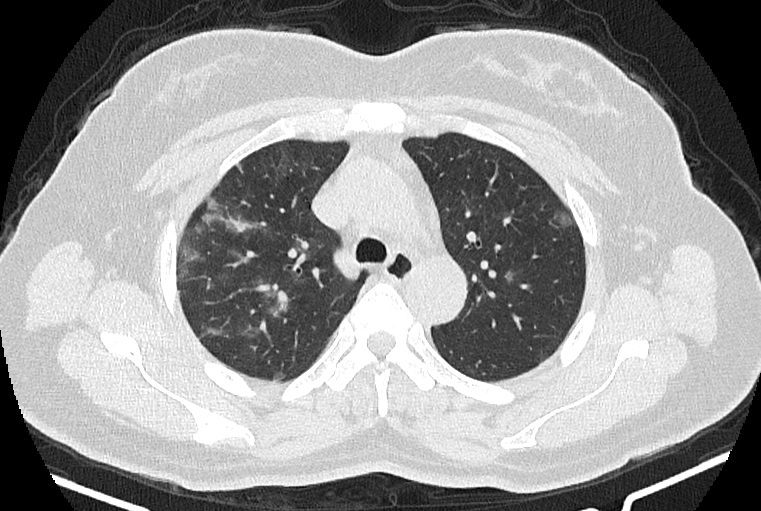

در HRCT از ريه ها(اسپيرال ، مولتي ديتکتور 16، مقاطع اگزيال با ضخامت 1mm بدون فاصله ) ، بدون كنتراست تزريقي :

-Ground glass opacities Patchy پراکنده در ريه ها مشهود است که مطرح کننده Viral pneumonia مي باشد . ( با درگيري 20 درصد حجم ريه )

نتیجه : Highly suggestive of COVID-19